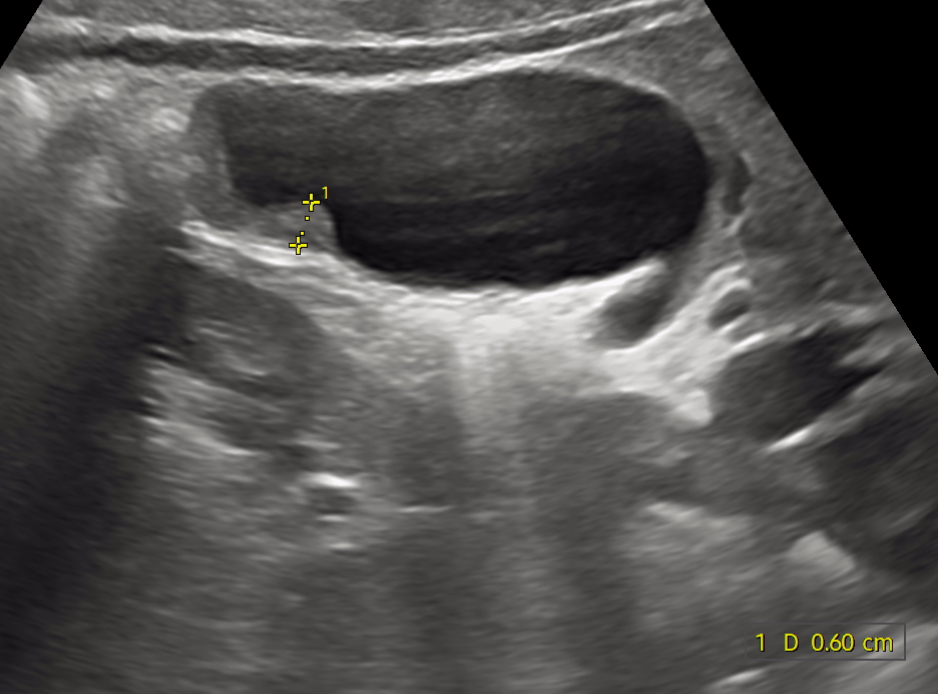

만 나이 25 남자입니다. 담낭암일 수 도 있나요? 가끔 과식할때 소화불량이 있어 우연치 않게 건강검진하다가 현재 초음파검사상 담낭벽비후 진단 받았고 ct결과 기다리는중입니다.

• 1번 째 사진